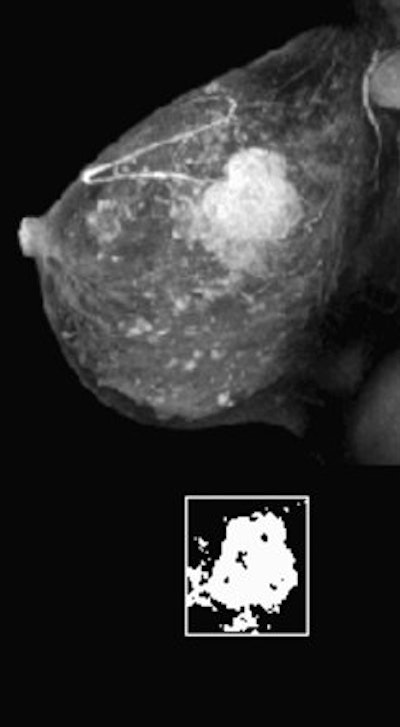

|  |

| Fifty-year-old woman with invasive ductal carcinoma, grade III, studied while undergoing neoadjuvant chemotherapy treatment. MRIL was performed using contrast-enhanced 3D fast gradient-recalled echo-pulse sequence. Patients presented with 22 cm3 (4.7-cm diameter) tumor. Significant reduction in MRI volume was evident after one cycle of chemotherapy (30% decrease) and by end of treatment (88% decrease). Patient had 2.2 cm of residual disease and one involved lymph node at surgery, and continues to be disease-free 20 months after surgery.  |